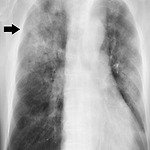

폐렴 증상, 감기 증상과의 차이

폐렴 증상, 감기 증상과의 차이 감기와 독감이 다르듯 폐렴도 다릅니다. 어떤 차이점 있는지 어떻게 구분할 수 있는지 미리미리 알아두셔야합니다. 폐렴 주 증상은 발열, 기침, 가래 등으로 감기와 아주 흡사합니다. 따라서 이 증상 만으로 둘을 구분하기란 너무 어려운 일입니다. 완전히 다른 병인 폐렴 그리고 감기는 그 증상은 거의 같지만 큰 차이가 있습니다. 바로 감염이 발생하는 부위입니다. 감기 발생 부위는 주로 코나 목 등 상기도가 원인 미생물이 감염되어 염증이 발생하는 것입니다. 이와 달리 폐렴 그 중 일반적인 폐렴의 경우는 폐 속의 감염으로 폐포라는 부위에 염증이 발생한 것을 말합니다. 폐포란 산소를 받아들이고 이산화탄소를 배출하는 호흡을 하고 있는 부분입니다. 따라서 이 폐포에 염증이 있으면 숨 쉬기..